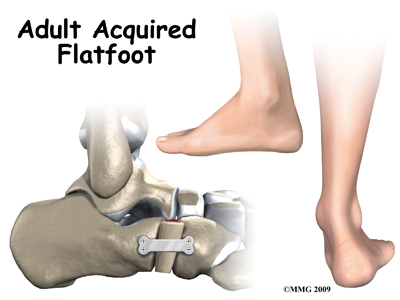

Adult acquired flatfoot deformity (AAFD) is a painful condition resulting from the collapse of the longitudinal (lengthwise) arch of the foot. As the name suggests, this condition is not present at birth or during childhood. It occurs after the skeleton is fully matured.

There are four stages of AAFD. The severity of the deformity determines your stage.

Stage I: There is a flatfoot position but without any deformity. Pain and swelling from tendinitis is common in this stage.

Stage II: There is a change in the foot alignment. This means a deformity is starting to develop. The physician or therapist can still move the bones back into place manually (passively).

Stage III: There is a fixed deformity. This means the ankle is stiff or rigid and doesn’t move beyond a neutral (midline) position.

Stage IV: Is characterized by deformity in the foot and the ankle. The deformity may be flexible or fixed. The joints often show signs of degenerative joint disease (arthritis).